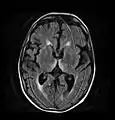

صورة محورية تظهر اشارة في المادة الرمادية المركزية وسقف الدماغ المتوسط.

صورة محورية عن طريق الرنين المغناطيسي FLAIR تظهر إشارة في الوسط المهادي ظهري ، وهو شيء شائع في الاعتلال الدماغي المرتبط بمتلازمة فيرنيك. كان هذا المريض تقريبا في حالة غيبوبة عندما بدأ تمديده بالثيامين وريدياً ، استجاب بشكل جيد لكنه ترك بعض العجز المرتبط بمتلازمة كورساكوف.